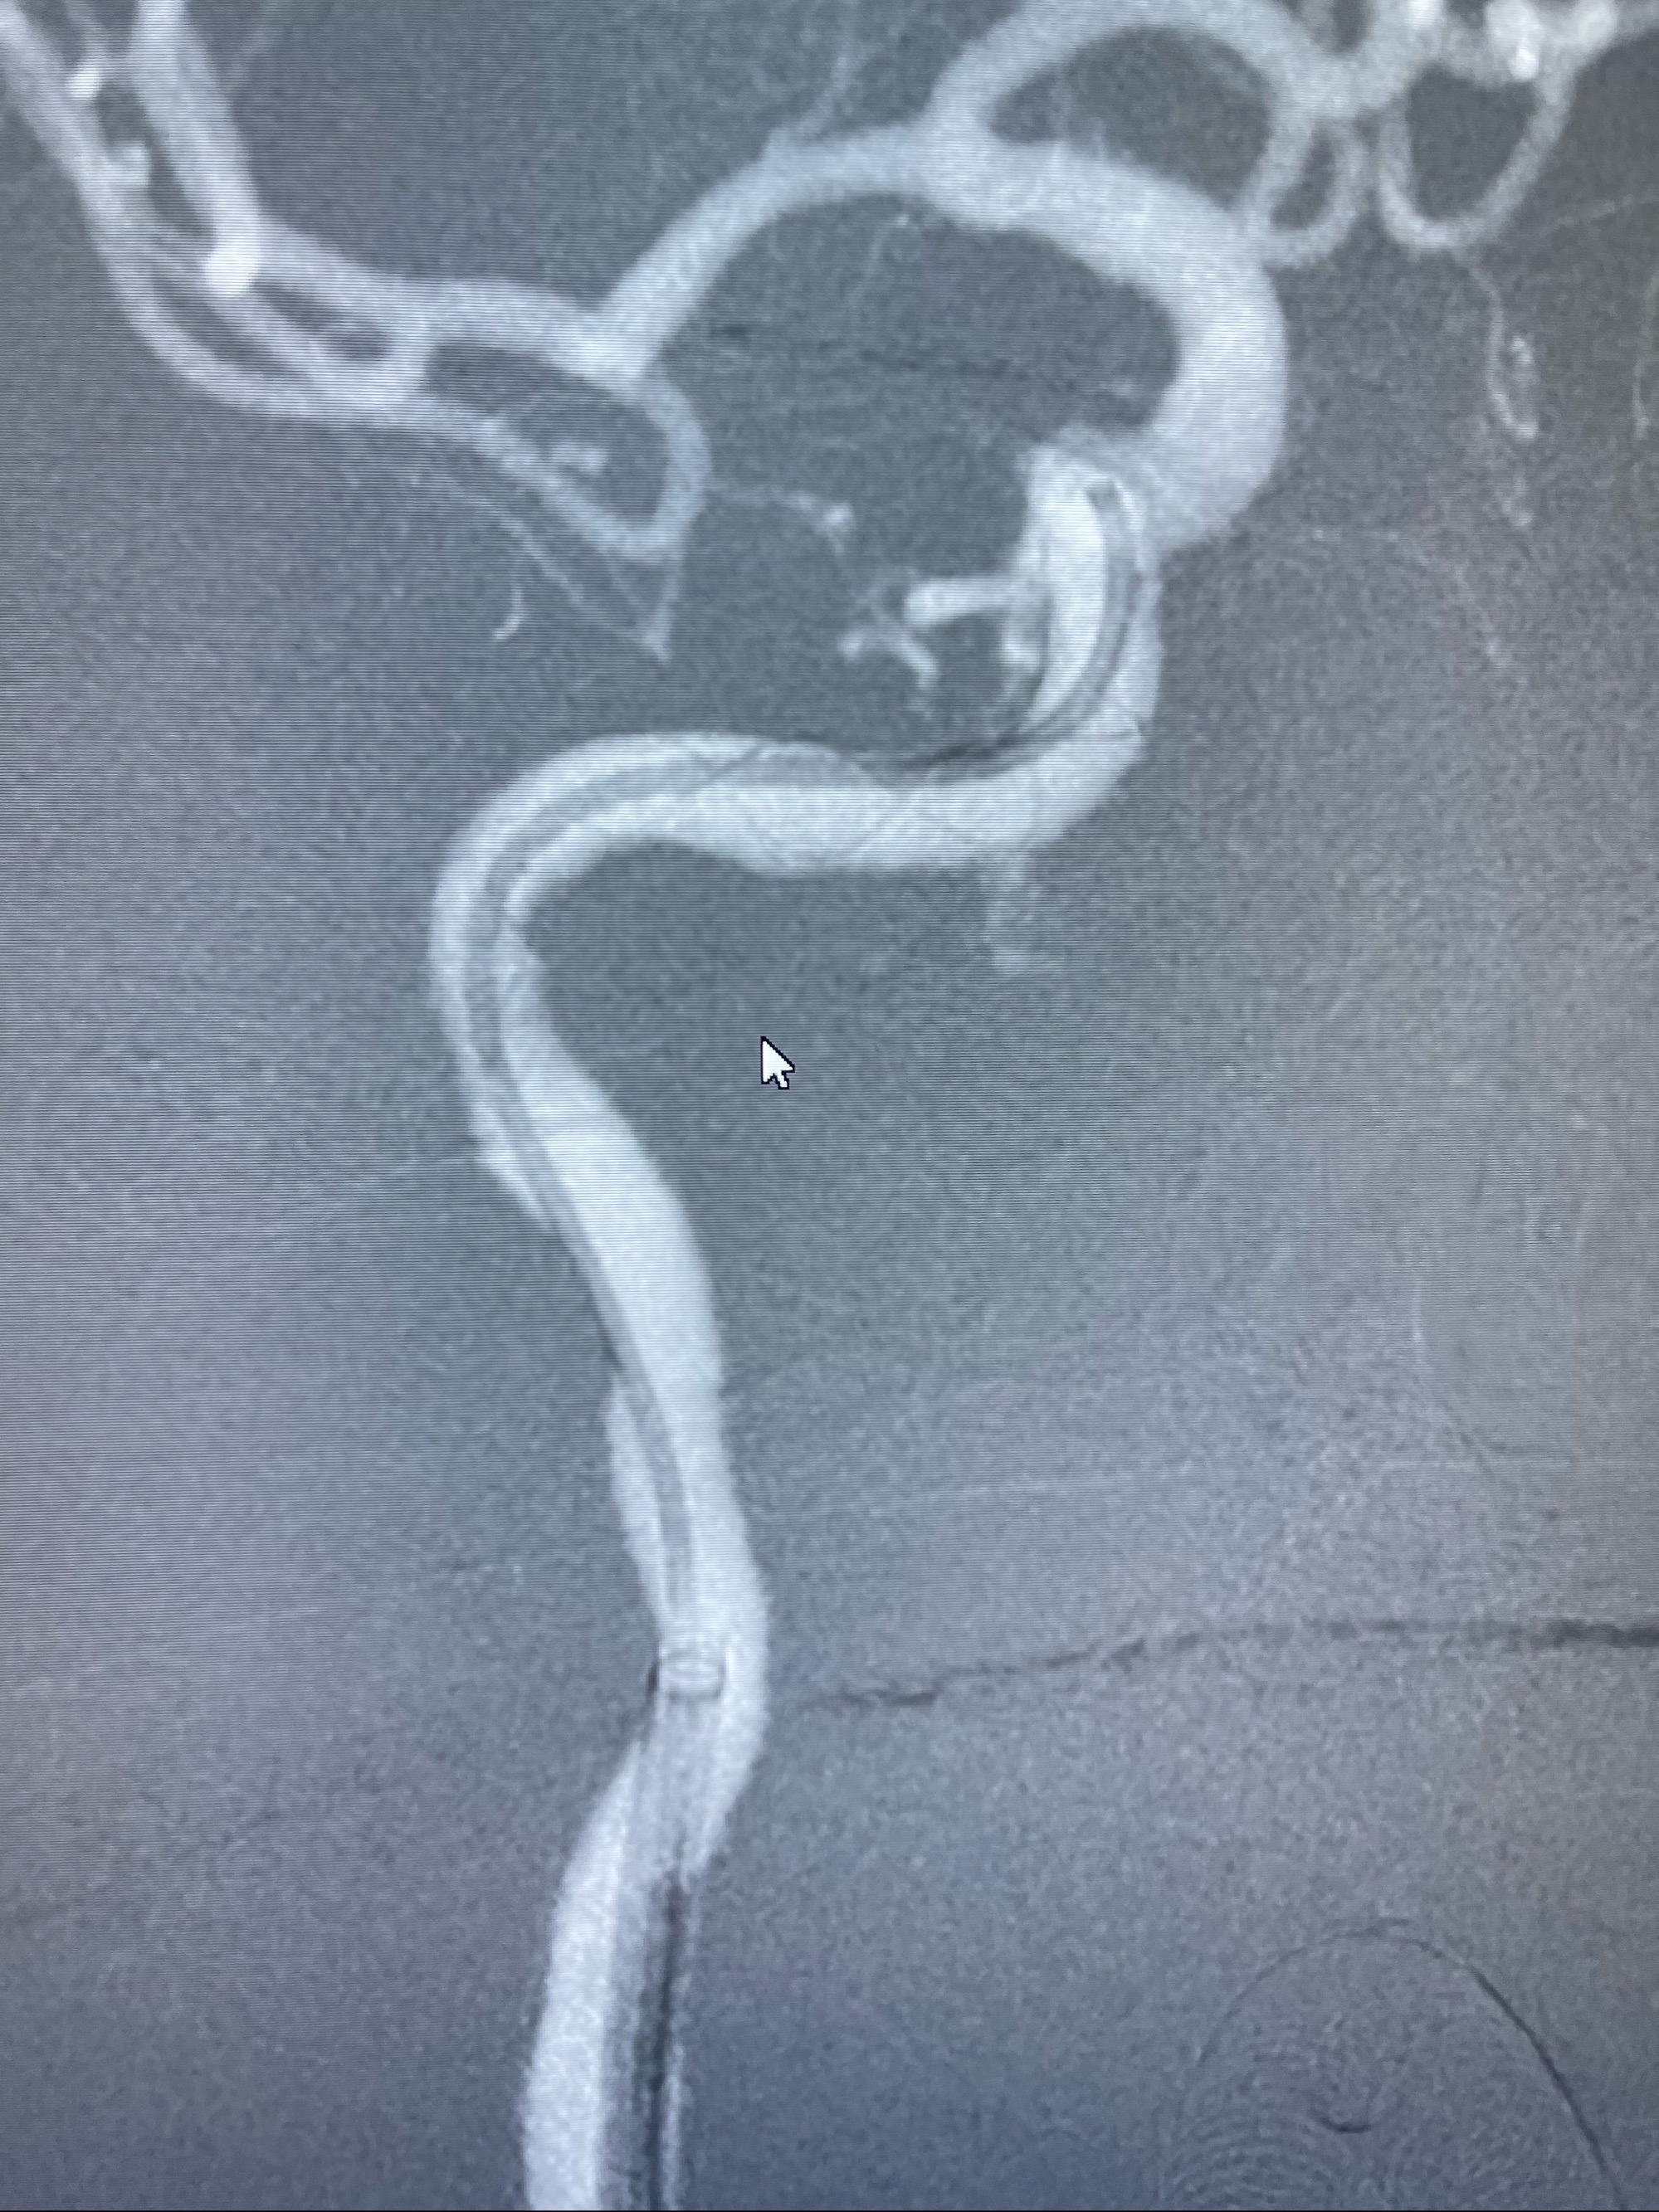

路径图下,5.5-50mmLeo支架导管在微导丝引导下超选择性插入远段Leo支架内

两枚支架部分重叠

多次确认支架位置及打开贴壁情况

支架完全打开,近心端位于原颈动脉支架远心端内

麻醉苏醒佳,遵嘱活动!